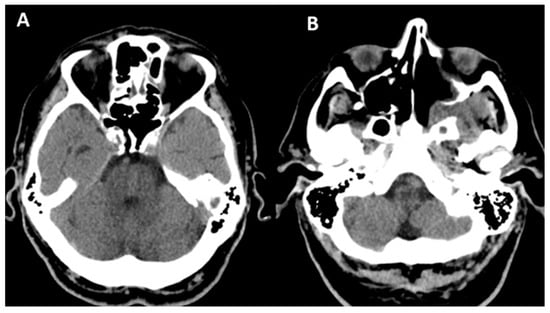

2.2. Case 2